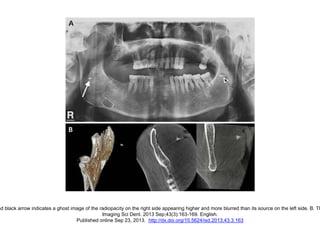

nd black arrow indicates a ghost image of the radiopacity on the right side appearing higher and more blurred than its source on the left side. B. Th

Imaging Sci Dent. 2013 Sep;43(3):163-169. English.

Published online Sep 23, 2013. http://dx.doi.org/10.5624/isd.2013.43.3.163